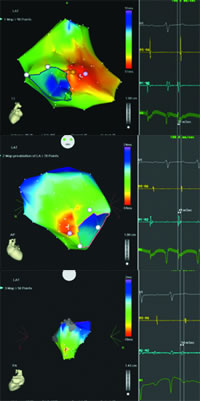

图3 右心房激动标测图 图4 左心房激动标测图 图5 主动脉根部激动标测图

图3:先行右心房三维重建及激动标测,见希氏束附近较大范围激动较早,右心房最早激动领先体表P波37 ms,单极标测局部呈rS型,试消融无效。

图4:左心房激动标测亦见前间隔区较大范围激动较早,左心房最早激动领先体表心电图49 ms,局部单极标测呈rS型,试消融无效。

图5:主动脉根部标测无冠窦激动最早,领先体表P波54 ms,单极标测呈QS型。

本病例显示,无冠窦起源房速心内标测的间隔区激动较早,其中,在右心房希氏束附近和左心房前间隔区激动最早,局部单极标测均呈rS型,消融不能成功。通过CARTO的三维重建及图像融合显示,无冠窦在空间上与右心房希氏束和左心房前间隔区邻近,离心室侧较远,而左、右冠窦分别邻近心室流出道,离心房侧较远(图9~11)。这也可能部分解释心房容易与无冠窦产生肌束联系,而左右动脉窦易与心室流出道产生肌束联系的现象。同时,正是由于无冠窦与左右心房间隔同时产生电学联系,使心动过速时左右心房最早激动时间差别较小,心内膜面较早激动面积较大。